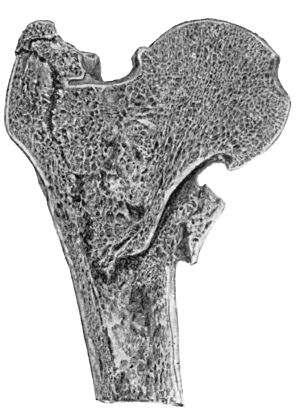

| 61. | Fracture through Narrow Part of Neck of Femur on Section | 131 |

| 62. | Impacted Fracture through Narrow Part of Neck of Femur | 132 |